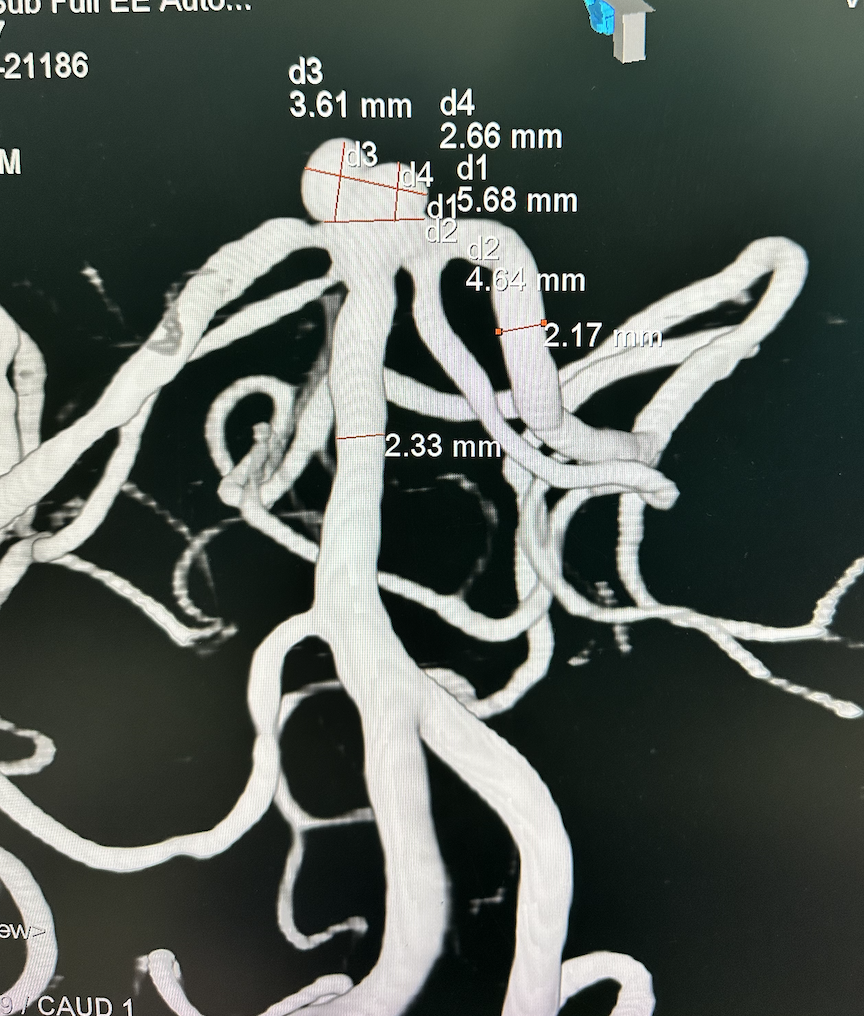

脑血管造影

基底动脉顶端动脉瘤,呈分叶状,瘤体5.6mm×3.6mm,瘤颈4.6mm

①基底动脉顶端动脉瘤,瘤体呈分叶状,形态不规则,宽颈,累及双侧大脑后动脉起始处,破裂风险高;